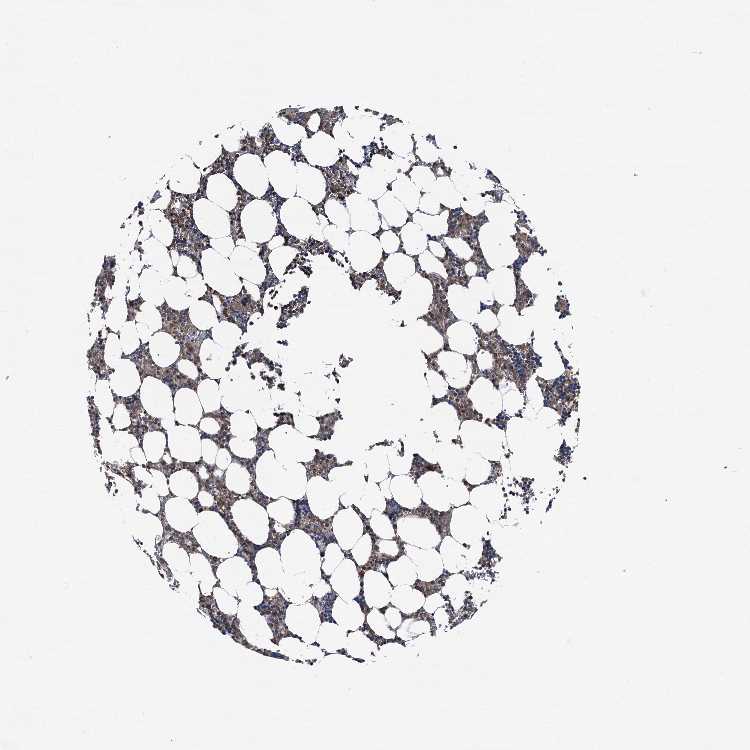

BONE MARROW - Antibody stainingi

Antibody staining in the annotated cell types in the current human tissue is reported as not detected, low, medium, or high, based on conventional immunohistochemistry profiling in selected tissues. This score is based on the combination of the staining intensity and fraction of stained cells.

Each image is clickable and will lead to virtual microscopy that enables deeper exploration of all samples and also displays staining intensity scores, fraction scores and subcellular localization as well as patient and tissue information for each sample.

Antibody HPA038804

Hematopoietic cells Medium